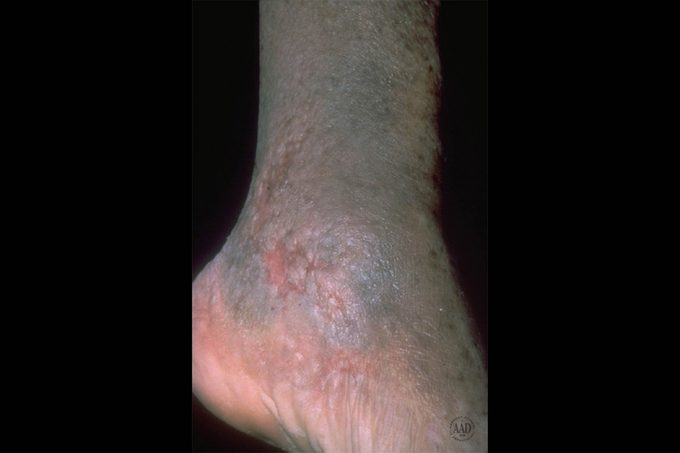

Poor vein circulation in your lower legs can lead to swelling and itchiness—called stasis dermatitis. Learn what you can do to relieve your symptoms.

Don’t stand or sit around too long

“Stasis dermatitis is caused by poor vein circulation in the lower legs,” says Melanie Palm, MD, a board-certified dermatologist and cosmetic surgeon at Art of Skin MD, in San Diego. The National Eczema Association says symptoms include swelling, scaling and dryness, leg aches and redness; more severe cases may involve oozing and infection. Unfortunately, a common habit may make intensify the problem, says Dr. Palm. “Excessive standing or sitting could worsen the condition.” Help your body recover from a day of sitting by following these easy steps.